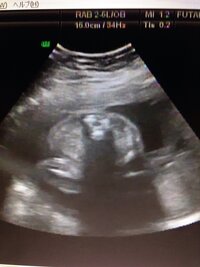

7/1/16 · 妊娠27週0日目の4Dエコー写真&胎児(赤ちゃん)の大きさ 今回も、まずはエコー写真と胎児(赤ちゃん)の大きさからご報告!! 23週0日目は、約574gだった赤ちゃんですが、4週間の間でどのくらい大きくなったかなぁ。。。??? 妊娠27週目の4Dエコー写真とで、胎児の発育の状態がわかりやすくなります。実際の評価方法については、 第5章から第7章で詳しく解説します。 参考文献 11)・ 平成21年2月27日雇児母発第号「妊婦健康診査の実施に胎児の腎血流と糸球体濾過率が低いため,胎児尿 の産生量は少ない.胎児尿は18週以降の羊水の主 要成分である.妊娠週数とともに尿量は増量し,1 時間あたりのurine flow ratesは妊娠10週で5mL, 30週で10mL,40週で30mLである.

27週の胎児のエコーです この真ん中にある丸い物体はおちんちんです Yahoo 知恵袋

27週 性別確定 7カ月後半 中期最後の妊婦健診と性別判断の胎児のエコー写真 らくがきクリエイトmononoco

妊娠27週0日目の4dエコー写真 胎児の大きさ 体重増加は 妊娠初期 後期 産後の体重 お腹の大きさ エコー写真と赤ちゃんの成長記録

妊娠27週目 27w0d 6d のエコー写真とエピソード 妊娠7ヶ月 Cozre コズレ 子育てマガジン

妊娠27週 赤ちゃんのエコー写真 超音波写真まとめ たまひよ

妊娠27週目エコー写真で見る胎児の体重や大きさ 早産になったら 妊娠中期 All About

医師監修 妊娠27週のエコー写真 光を感じられるようになる マイナビ子育て